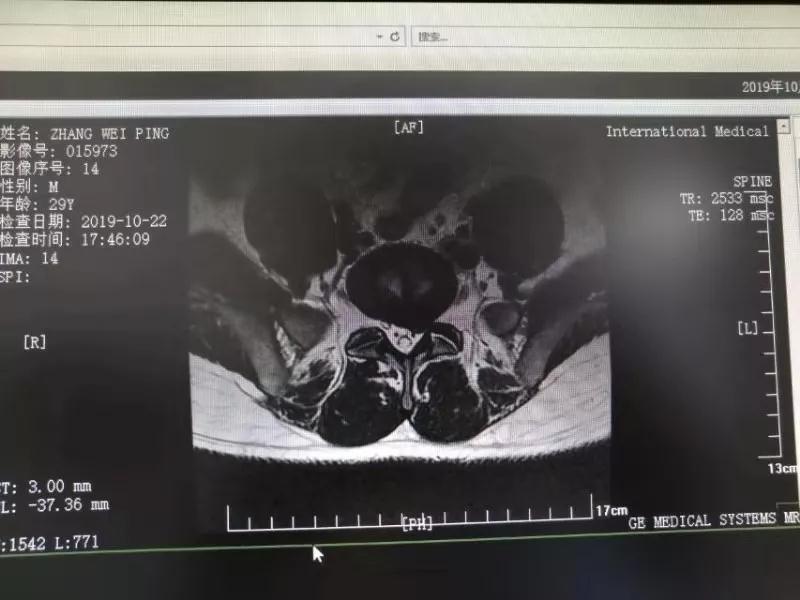

10月25日,29歲的患者小張了解到西安國(guó)際醫(yī)學(xué)中心骨科醫(yī)院專家云集,一大早便在家人的陪同下,來(lái)到西安國(guó)際醫(yī)學(xué)中心骨科醫(yī)院就診?!拔已闯掷m(xù)2年多,最近感冒后腰痛癥狀明顯加重了?!毙埫媛犊喑?,因?yàn)殚L(zhǎng)期腰痛、左下肢放射性疼痛,她晚上睡覺(jué)不能平躺,經(jīng)常疼得睡不著,需要口服止痛藥物才能有所緩解。走路走不了多遠(yuǎn)就開(kāi)始腿抽的疼,嚴(yán)重影響到工作和生活。

結(jié)合患者的檢查以及年齡情況,王自立副院長(zhǎng)推薦讓專門(mén)研究椎間孔鏡技術(shù)王雄勛主任給小張做微創(chuàng)的椎間孔鏡手術(shù)。該手術(shù)創(chuàng)傷很小,不影響脊柱的穩(wěn)定性,尤其適合于椎間盤(pán)突出的年輕患者,懷著對(duì)骨科醫(yī)院專家的信任,小張與家人商議后,接受手術(shù)治療。